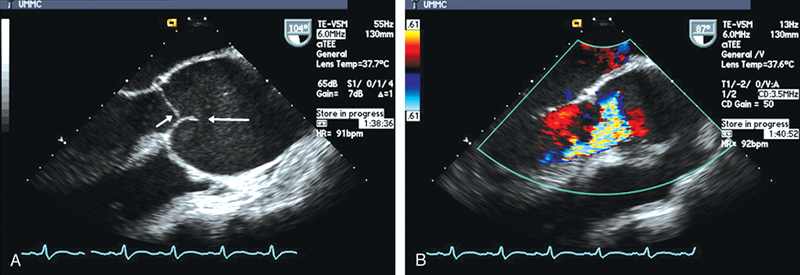

فحوصات تشخيصية لبعض امراض القلب والشرايين التاجية